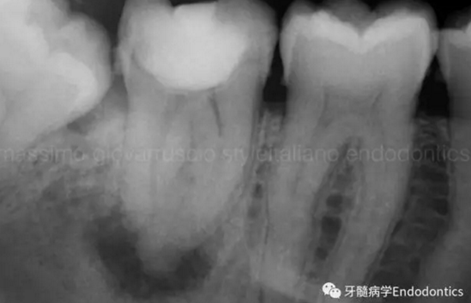

圖7.具有解剖障礙的根管,比如根尖區(qū)不規(guī)則的直根管、存在不規(guī)則急彎的彎曲根管。

圖8.這個根管需要智慧和毅力才能越過。難點在于通過在觸覺(通過手用器械傳來的感覺)感受到銼在根尖的阻力。這會發(fā)生是因為銼的尖部會被不規(guī)則解剖形態(tài)干擾,而不是銼到全長并超出。

圖9.當遇到了根尖方向的阻力,退出銼,使用銼預彎鉗(Endobender)平滑的預彎銼尖部的2mm,將銼上的硅膠止動片的方向指示調成朝向銼彎曲的方向,這樣你就可以繞過障礙形成通路了。

圖10.探查時小心地使用給手表上發(fā)條的動作使銼向前通過障礙。遇到阻礙時,稍微回拉銼,將銼尖轉向新的方向,向根尖方向扭動,觀察銼是否前進。如果沒有,將銼回拉,重新將彎曲的銼尖改變方向,觀察是否通過。不斷重復,觀察是否前進,直至通路形成。必須使用根測儀和X線片檢查在障礙通過后是否到達了根尖止點。